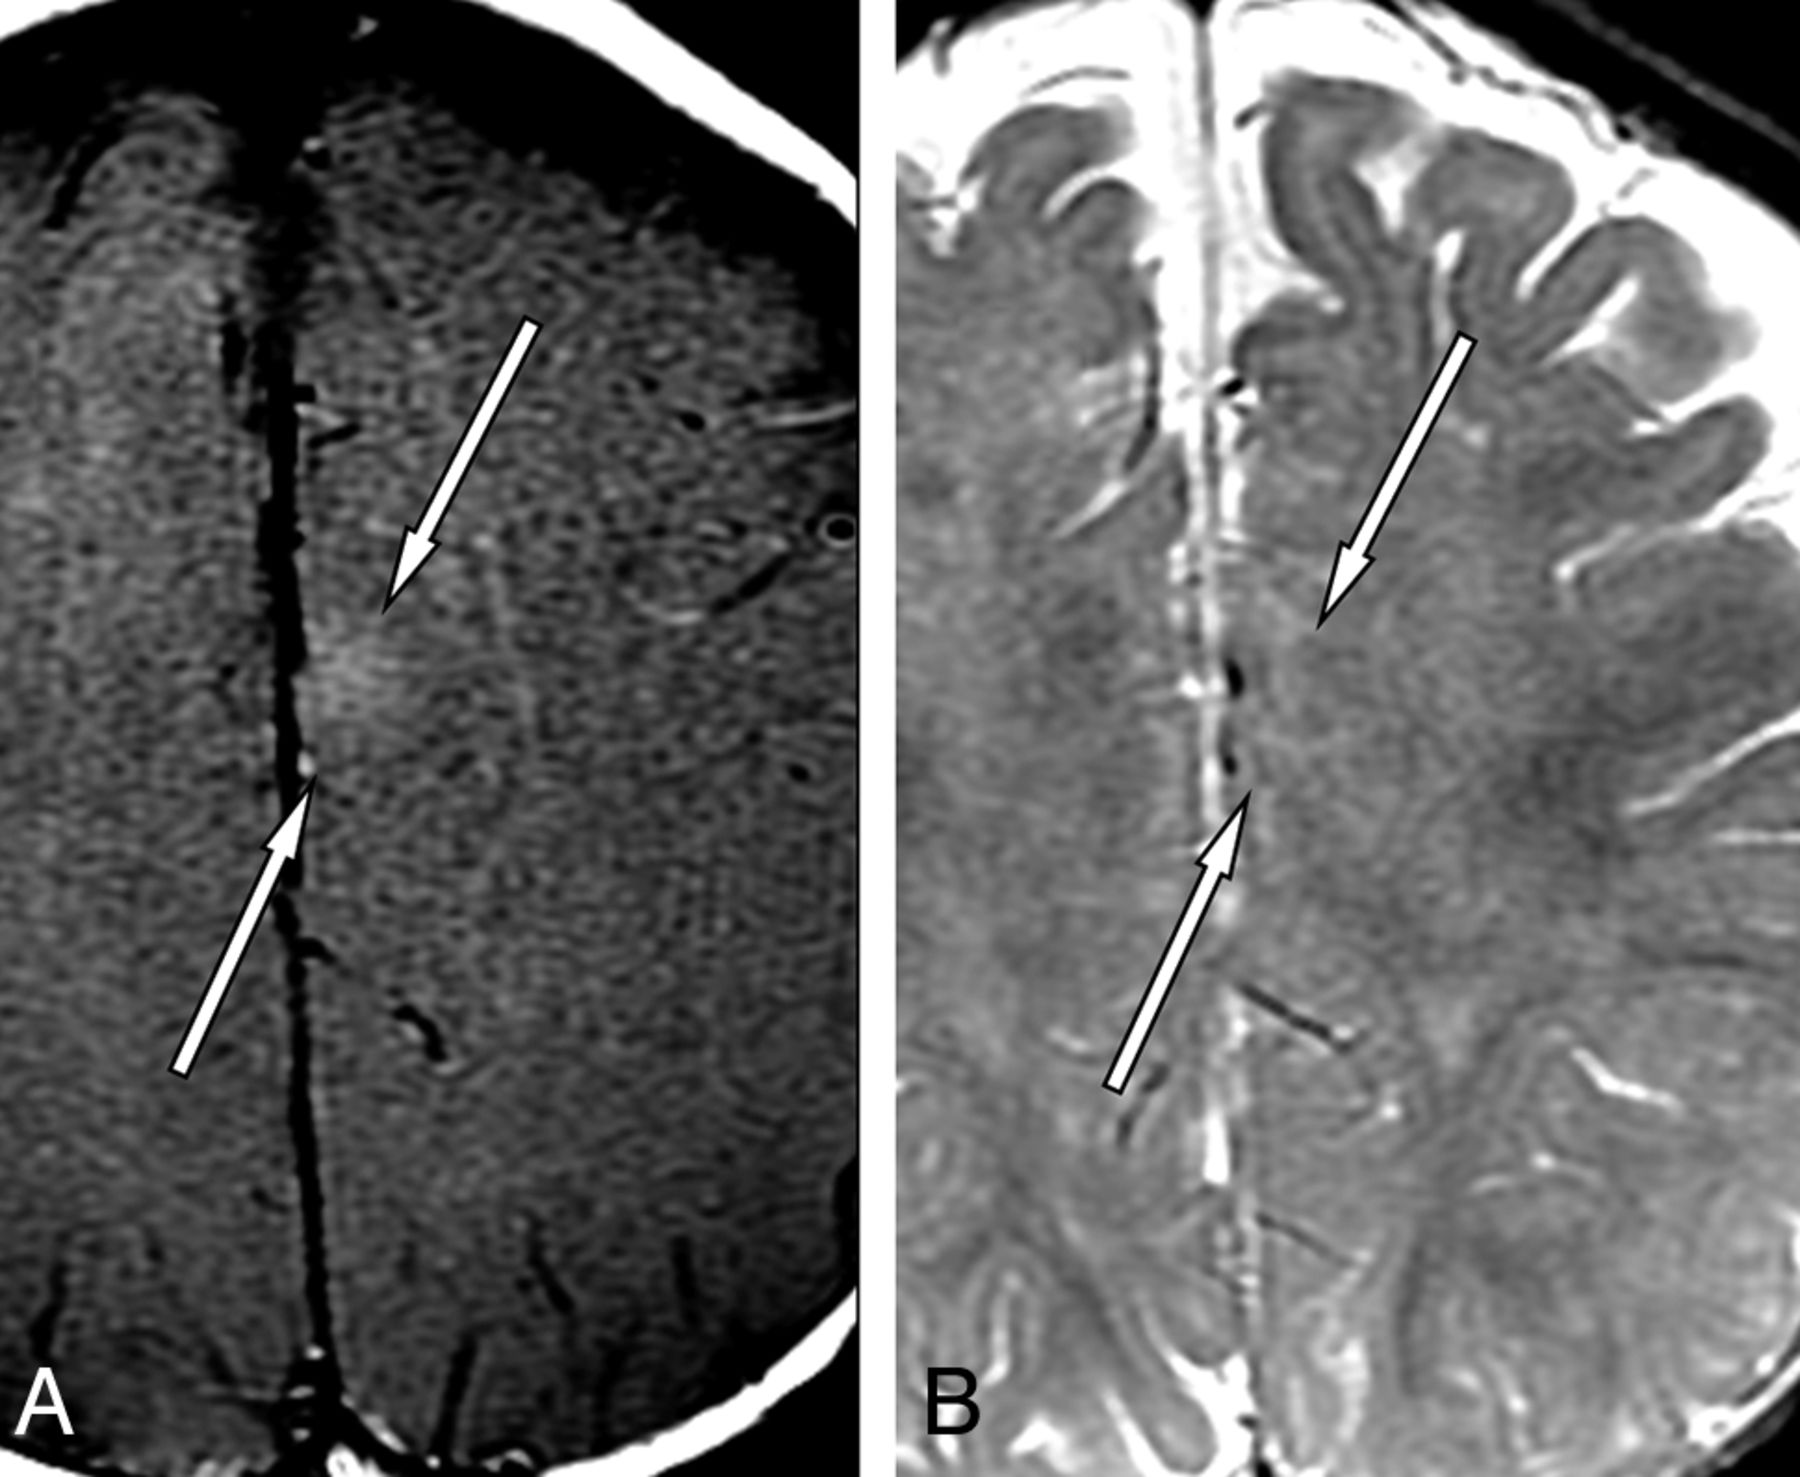

A 9-year-old boy presented with newly diagnosed seizures and a right anterior frontal focus on EEG (Fig 3). The usefulness of MT is that cortical dysplasia is best seen on MT T1 and is not readily identified on any other sequence because of its subtle nature and masking by superimposed artifacts from patient motion.

A 9-year-old boy with seizures and a right anterior frontal focus on EEG. MR imaging axial T1 with MT (A) and axial T2 (B). T1 with MT shows a linear hyperintense lesion in the right frontal lobe, extending from the subcortical white matter toward the ventricular wall (arrows, A). On the axial T2 image, the lesion is less well-visualized (arrows, B). The findings are compatible with focal cortical dysplasia (diagnosis confirmed clinically).